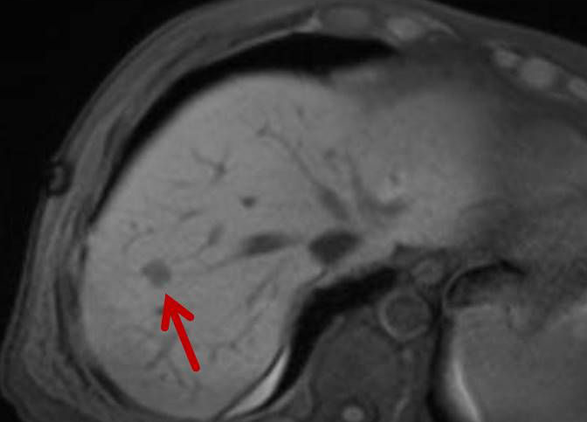

Abbildung: Bei diesem Patienten wurde ein im Röntgen nur schlecht sichtbarer Knochentumor vor der Operation unter MRT-Kontrolle mit kleinen röntgendichten Spiralen („Coils“) markiert. Damit hat der Operateur eine optimale Darstellung des Tumorbereichs bzw. der Tumorgrenzen und kann gezielter, schonender und effektiver operieren.